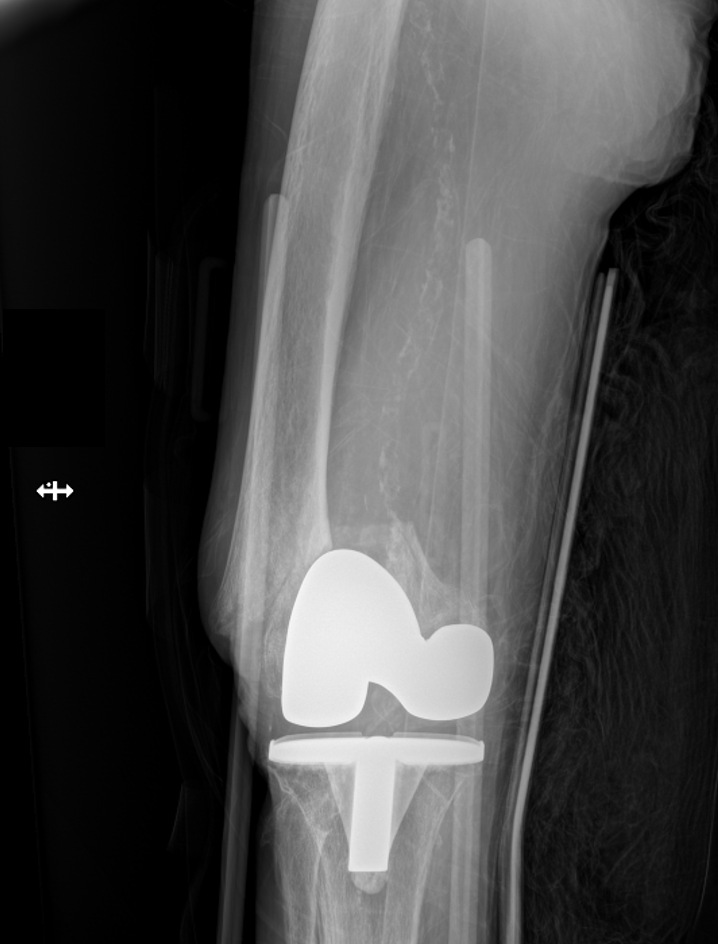

An 86-year-old male after a low-energy fall onto the right knee with a periprosthetic distal femur fracture above a TKA. These cases are getting more common, and the real challenge is not whether to operate—it’s choosing the construct. Nail? Plate? Dual plate? Nail-plate combo? Or do you skip fixation and replace it? For me, the decision tree starts with 3 questions: 1. Is the femoral component stable? 2. Is the femoral box actually nail-compatible? 3. Is the distal segment/bone stock strong enough for single-implant fixation? What would you do here? @orthobullets @medbullets orthobullets.com/Site/Cases/Vie…

Jan Szatkowski tweet mediaJan Szatkowski tweet mediaJan Szatkowski tweet media